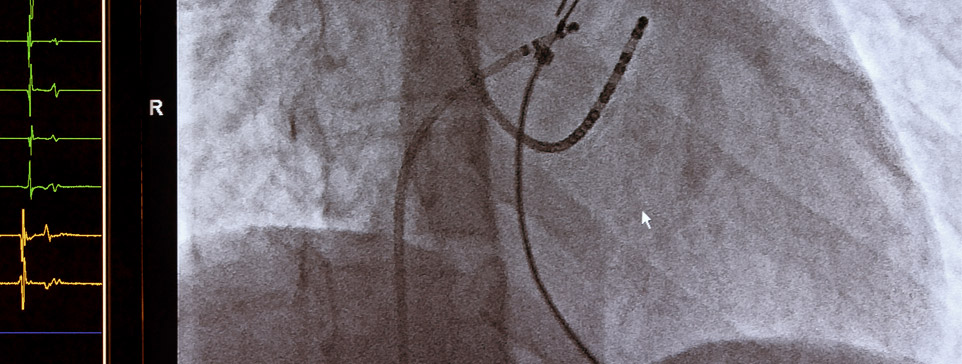

Ela trata as doenças vasculares por dentro dos vasos sanguíneos. Ocorre por punções ou pequenas incisões nas quais são introduzidos cateteres guiados por imagens de raio-x. Trata-se de um método eficiente e menos agressivo da medicina moderna.